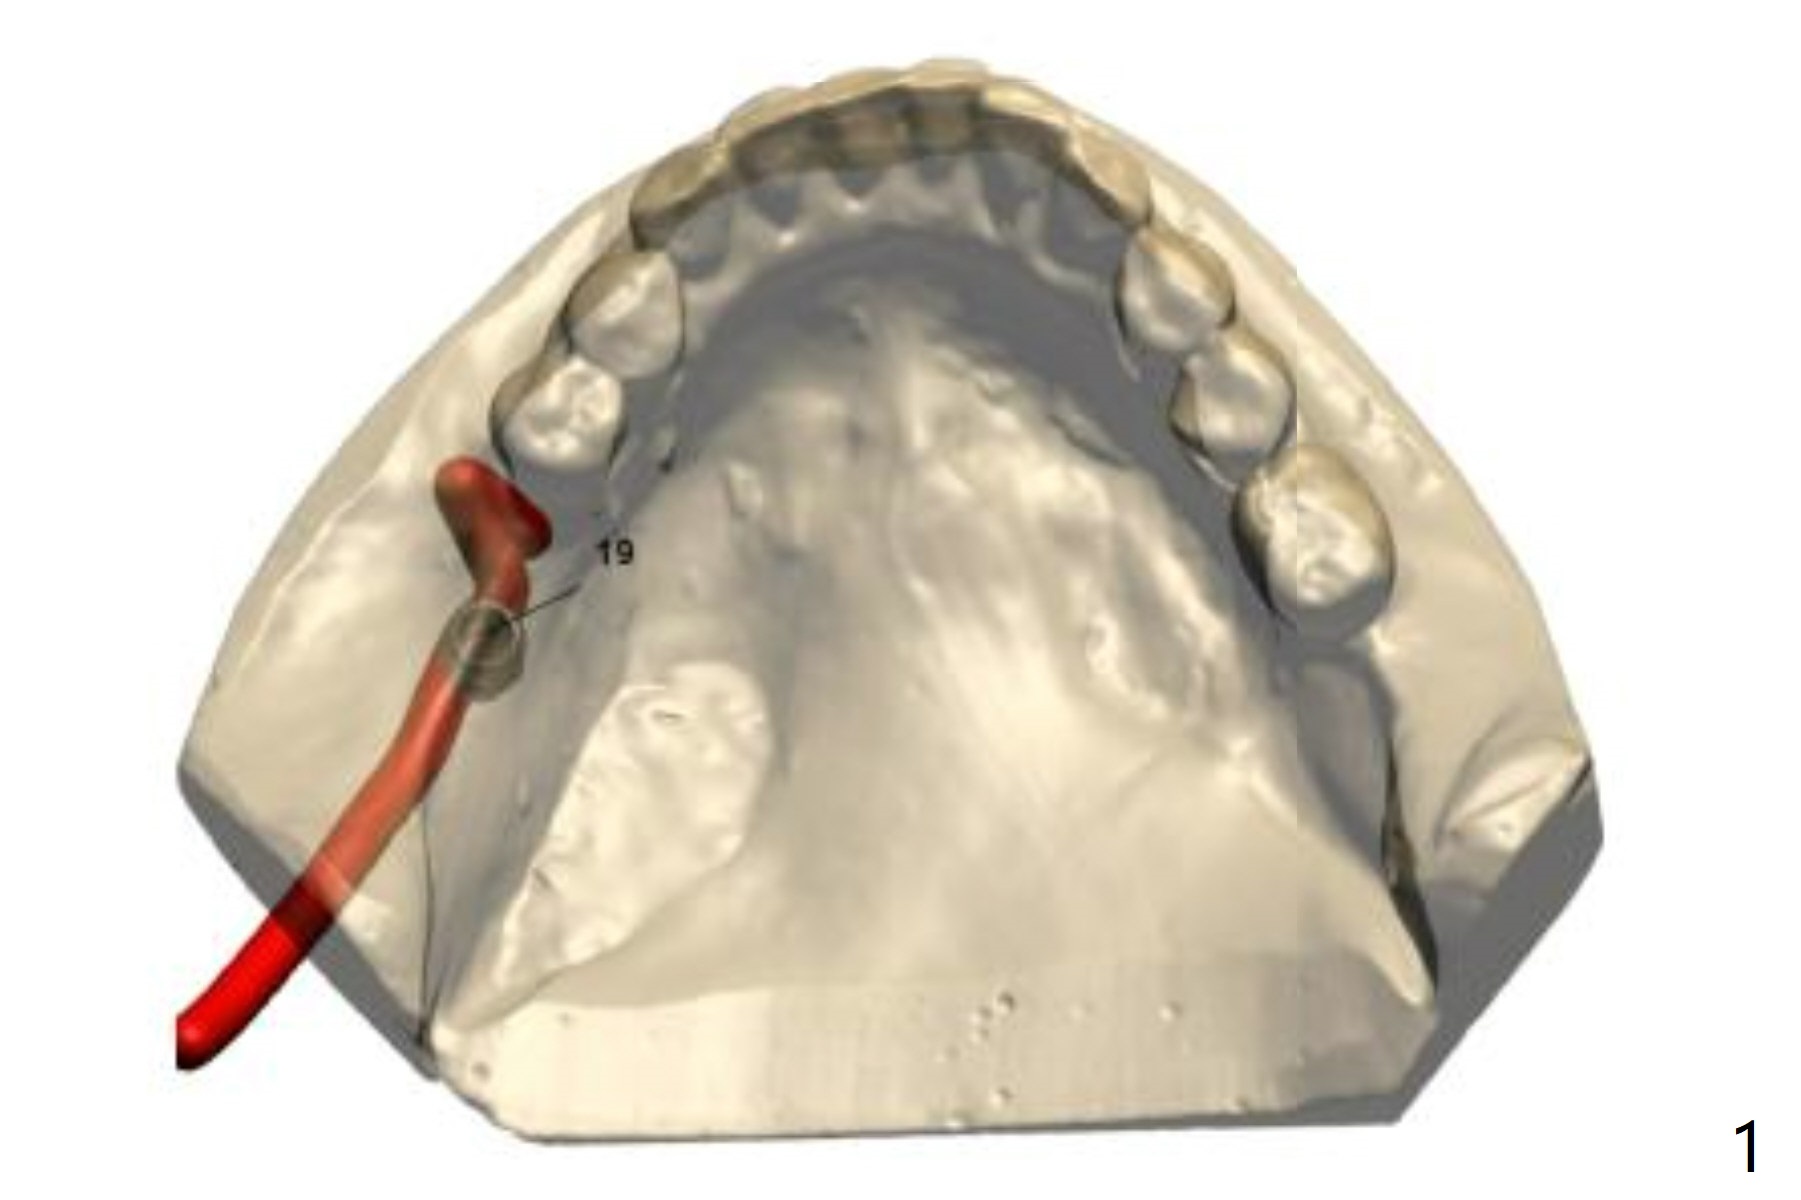

I have put 2 sets of surgical guides. Ones that I wrote as mounted are the ones fit on the mounted model with diagnostic wax up.

The first poured original models are indicated as patient name only. Try both and let me know how it went.